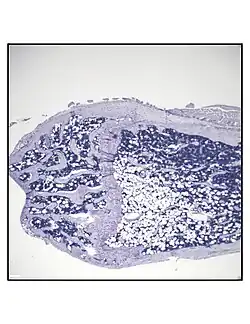

Secção histológica representativa da porção distal do fêmur de um camundongo C57BL/6 saudável de 16 semanas de idade, demonstrando uma quantidade típica de adipócitos na medula óssea. -